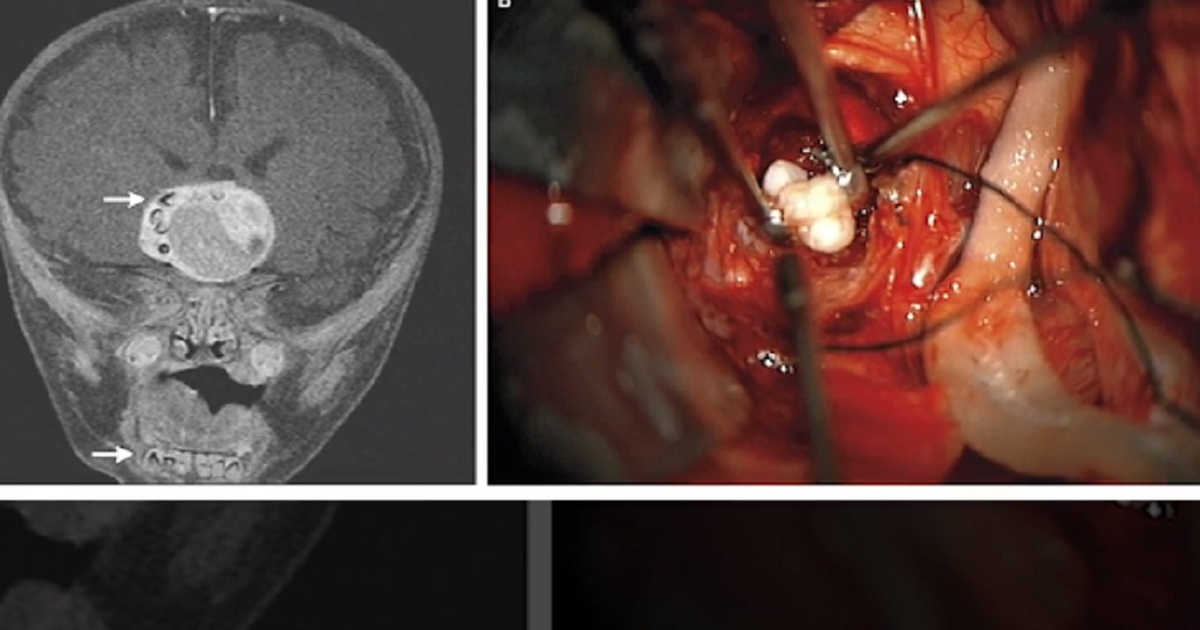

Bé trai 4 tháng tuổi ở Mỹ mắc một khối u kỳ lạ trong não. Sự kỳ lạ của khối u không chỉ dừng ở vị trí của đó. Bên trong khối u, một chiếc răng người phát triển hoàn chỉnh được tìm thấy.